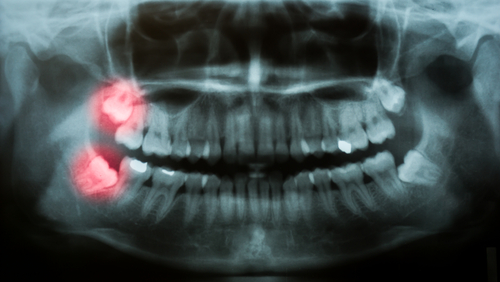

wisdom teeth on x-ray

The top reason why most wisdom teeth need to be removed is that there’s simply not enough room in the mouth for these new teeth. Your dental x-rays will show your dentist whether or not there will be enough space for your wisdom teeth. However, if your mouth doesn’t have adequate room and you do not have your wisdom teeth removed, it can lead to overcrowding, crooked teeth, or even an impaction. Having impacted wisdom teeth essentially means that the teeth are stuck in your bone below the gum line. This can be very painful and increases the risk of infection.